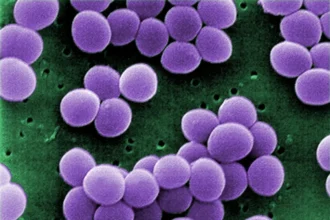

Bactéria resistente ultrapassa hospitais e acende alerta para saúde pública

Uma bactéria historicamente associada a infecções hospitalares começou…